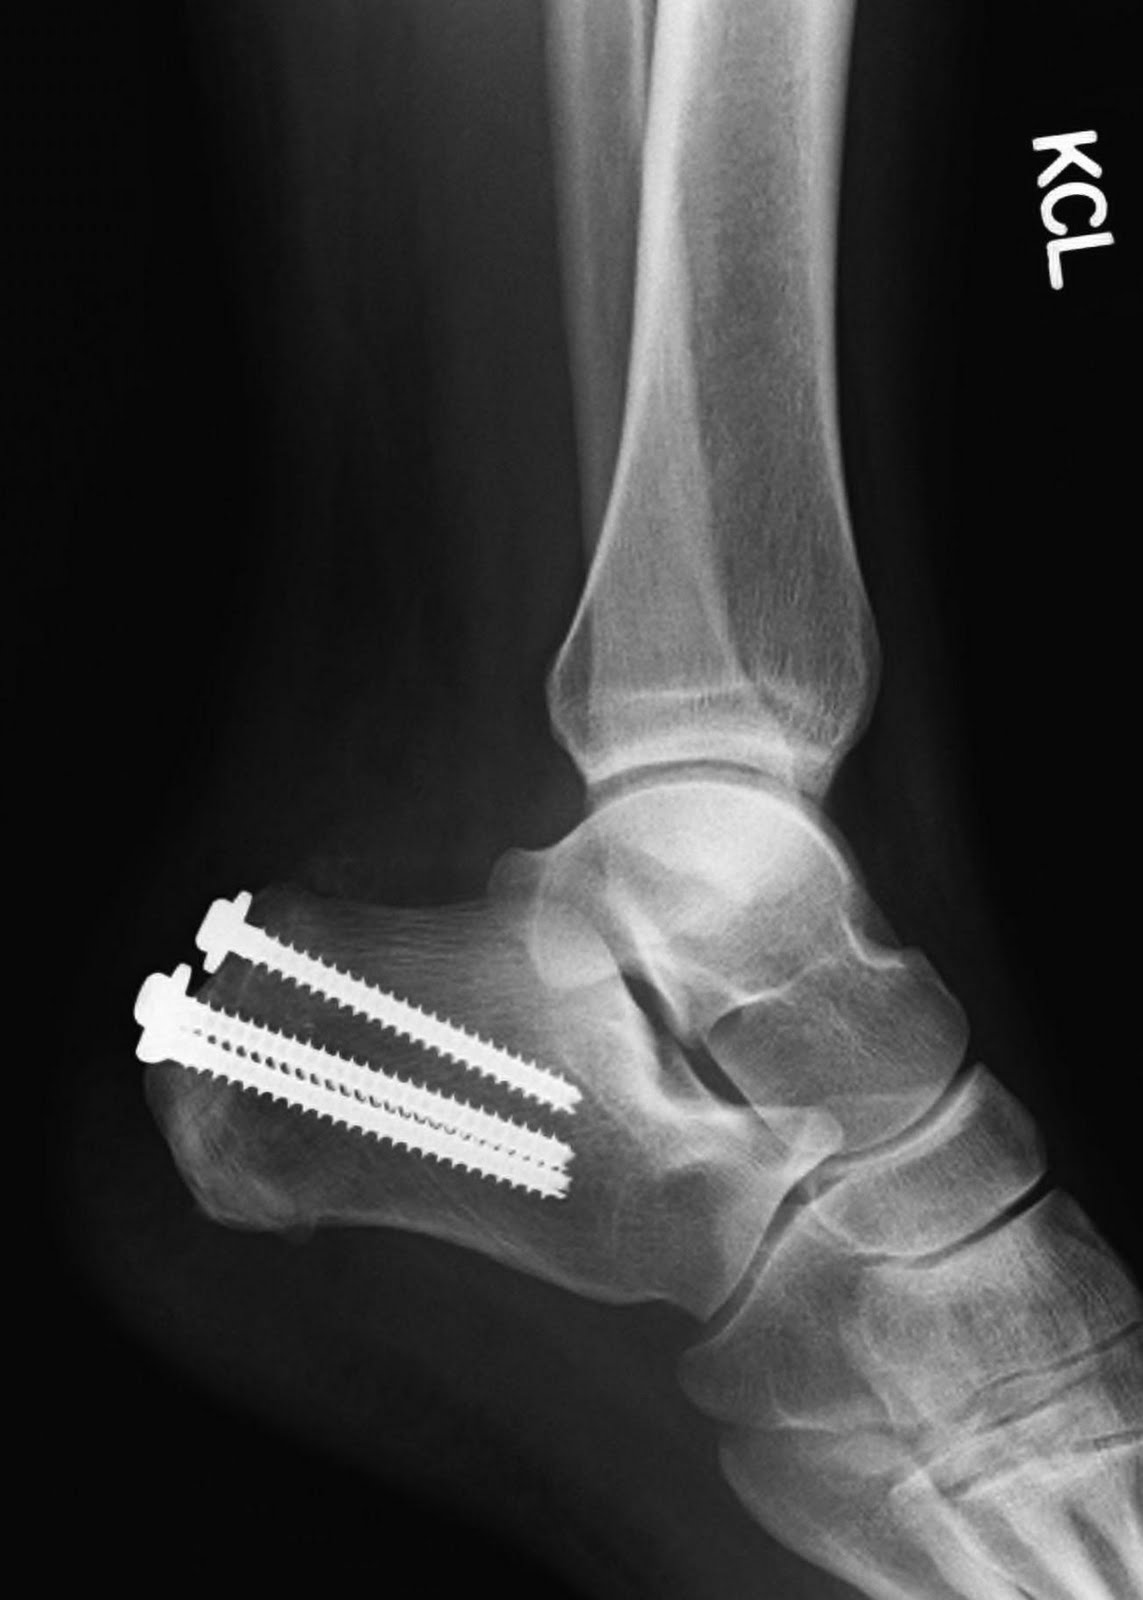

The bone has compleatly fused back together and I've never seen Dr.D so happy. He is almost giddy as he shows me the lack of any fracture lines on the x-ray.